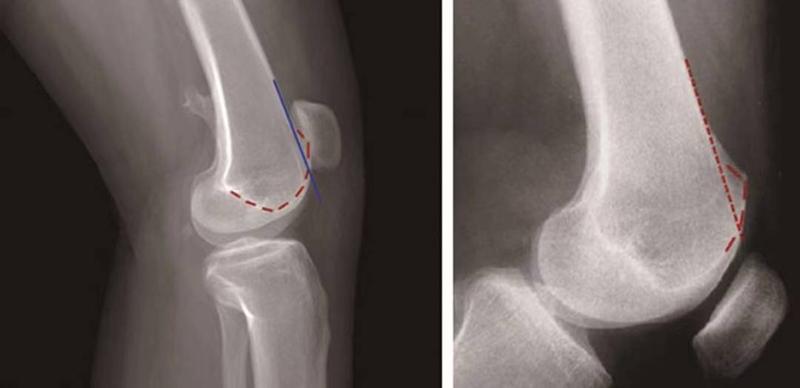

②突起征:

H.Dejour在1996年提出突起征(spur或bump)或滑车近端突起征(supratrochlear spur),是指在膝关节标准侧位像上,股骨滑车沟基底线的最高点位于股骨前方皮质延长线的前方(图12)。这种征象的实质是股骨滑车近端的整体抬高。在膝关节屈曲早期,髌骨必须越过滑车近端的突起才能进入股骨滑车,因此,容易出现髌骨向外脱位。如果突起征>5mm即为异常,意味着股骨滑车基底高于股骨外髁的轮廓。

图12 突起征

③*轨双**征(或称为双线征):

是指在膝关节标准侧位像上,代表股骨内外侧滑车的两条线分开,呈*轨双**样(图13)。它的出现提示股骨内侧滑车发育低平,导致它的前缘出现晚于外侧滑车。

图13 *轨双**征